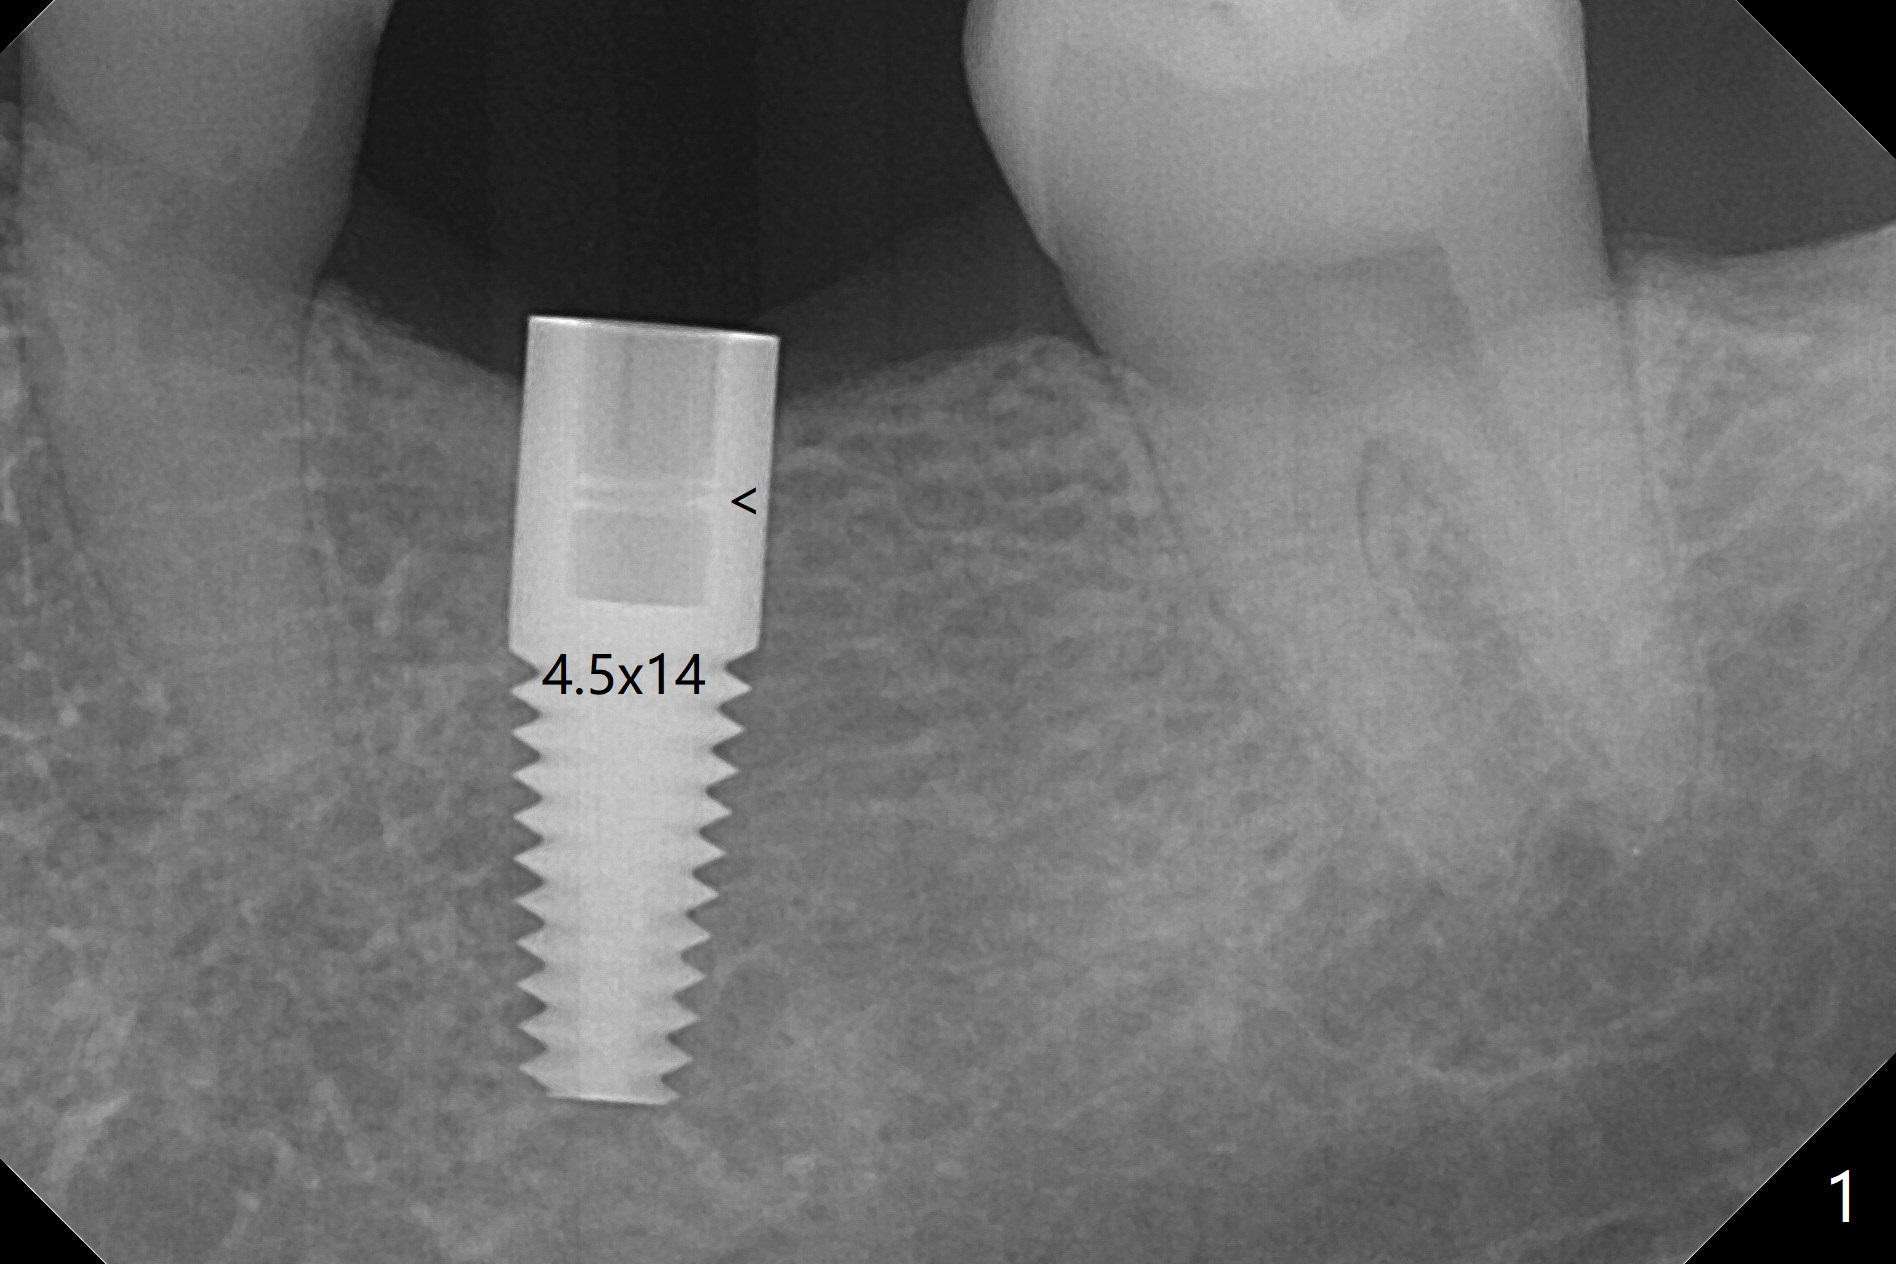

After 4.0x10 mm drill with 9 mm offset for 4.5x10 mm bone-level implant at #19, a 4.5x17 mm tissue level tap is inserted with apparently low torque (probably without reaching the depth). When a 4.5x14 mm tissue level implant is placed with high torque, a 4.5x7.3 mm drill is used for ~ 6.5 mm. The implant loses the primary stability with over-insertion (Fig.1). When an abutment is placed, the implant is critically loose. Mixture of autogenous bone, Osteogen and allograft is placed in the osteotomy. The implant regains stability with better placement level for restoration (Fig.2). In fact the bone density around the implant increases (Fig.2 *). For the first 7 days postop, the patient has to take Advil. When he returns for follow up 8 days postop (Fig.3), the pain decreases, while there is minor degree of lower lip paresthesia. Medrol Dose Pak and Tylenol III are prescribed. The implant is loose 24 days postop; after removal of the implant and apparently infected bone graft, a 7x14 mm dummy implant is inserted with <20 Ncm and 3-4 mm clearance (Fig.4). A longer dummy implant seems to improve stability (Fig.5). So does the definitive implant (Fig.6,7, 25 Ncm), but it is placed low. The gingiva looks healthy 13 days postop (2nd placement). A healing cap will be placed for restoration ~ 3 months postop. CT will be taken if the implant needs to be backed up to determine whether there is enough bone buccolingually. Due to coronavirus and prolonged placement of a healing abutment with poor oral hygiene, the buccal gingiva of the implant is erythematous 1 year postop (Fig.8 healing cap just removed) with bone loss (Fig.9,10 *). Sticky bone seems to be necessary. A 6x5 mm abutment with slots will be placed to hold periodontal dressing in place.